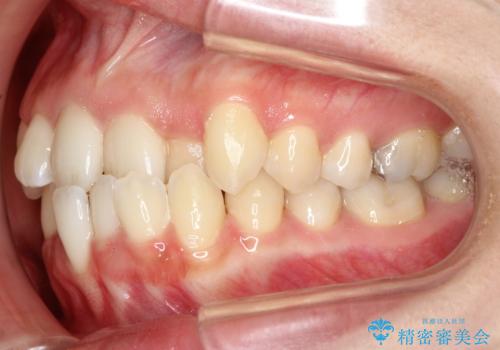

初診時の歯並びの状態としては、上下ともに全体に及ぶの中等度以上のがたつき(叢生)があり、前歯数本が反対交合の状態でした。

強い叢生がありましたが、抜歯は行わず上下顎ともに、主に歯列弓の拡大とディスキング(歯と歯の間に隙間を作る処置)を行い叢生を改善しました。